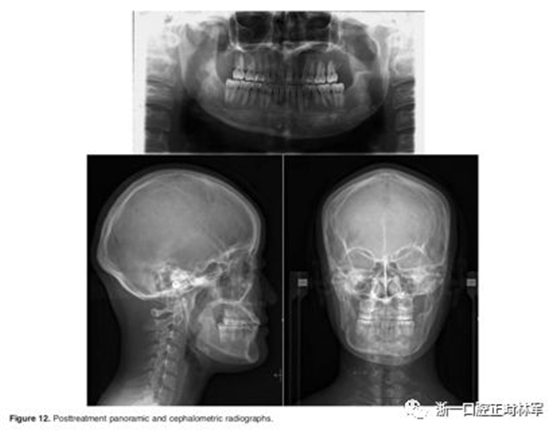

治疗后的头影测量和全景片如图12所示。面部不对称得到改善。牙列中线与面部中线对齐,上下颌拥挤得到解除(图13)。骨性III类关系得到改善(图14)。然而,由于III类关系并未完全矫正,所致的牙齿代偿使得上前牙变得前突。咬合关系改善,双侧尖牙Ⅰ类关系,并建立了理想的覆合和覆盖关系。在双颌手术后一年,固定钛板拆除,左下颌边缘切除2mm的皮质骨突起。随后,她的下颌骨的左右即恢复对称。下颌运动轨迹稳定,尖牙引导合,面部肌肉活动得到很好的平衡(图15)。术后六个月,Semmes–Weinstein评分为1,下牙槽神经瘫痪。

治疗后和保持后(治疗后两年)的头影测量照片叠加几乎没有变化(图16 - 19)。此外,在治疗前和一年后两次颌骨手术后获得的计算机断层扫描图像的叠加显示了骨骼中线的对称性,并且左侧髁突的大小没有改变(图20)。治疗后2年,咬合保持稳定(图16和17)。治疗过程中头颅测量变量的变化见表1。